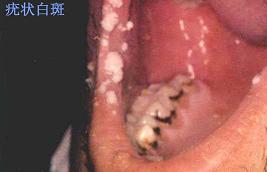

口腔粘膜病组图